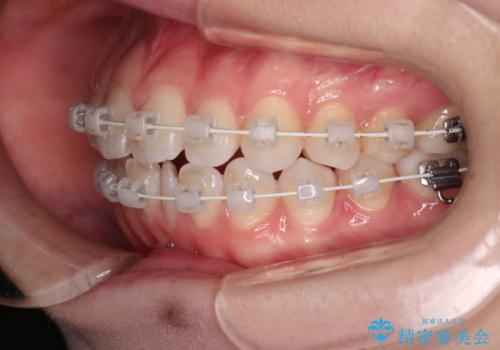

- 矯正装置

- 審美装置

ワイヤー矯正を行いながら、顎間ゴムを患者さまにご協力していただき、短い期間で終了できました。